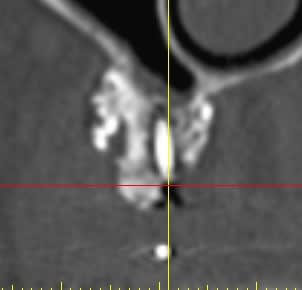

suite à divers soucis, manque d'os secteur 1, prélèvement ramique, + biooss, + vis ostéo + mbrane.

image à 6 mois

parmi les utilisateurs de biooss, avez vous déjà rencontré ce genre d'image?

et que vais je trouver ?

Pourquoi pas ? C'est très utile. Tu as vu le résultat ? Pas possible de planter dans cette masse non-homogène. Moi j'y toucherai pas.

D'aprés ce que je vois, il semblerait qu'il n'y ait pas eu de greffe d'apposition à proprement parlé, mais utilisation d'une portion de corticale en occlusal pour maintenir le bio-oss.

Si ce que je vois à gauche est une vis, elle s'est mobilisée et tout le reste avec.

Il semblerait qu'il y ait eu , de plus, colonisation de la greffe d'une part via la vis qui transperce le sinus, et d'autres part part la dent adjacente ( image radio claire autour de cette dent).

Personnellement je pense que la greffe n'a pas fonctionnée et que ton confrère va se retrouver dans une bouillie inutilisable.